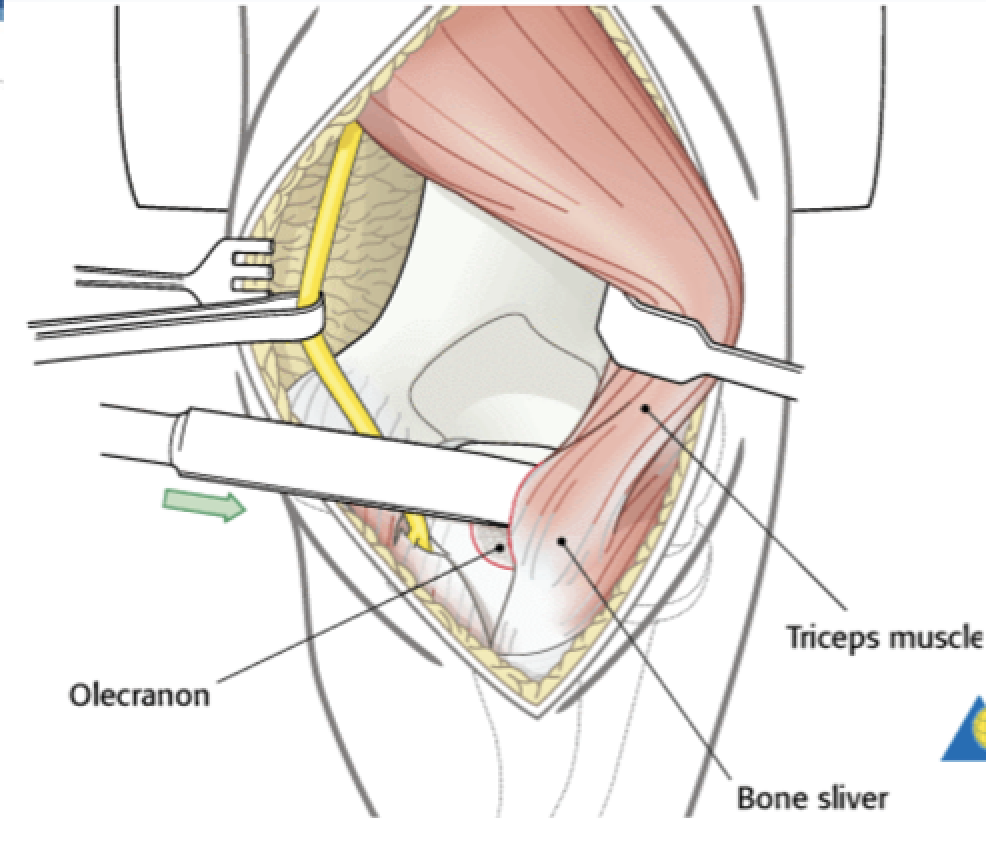

Olecranon Osteotomy

Interval: n/a

Approach: Apex distal osteotomy ~2cm distal to olecranon tip. Into “bare area” of sigmoid notch. Saw 1/2- 2/3 of the way in, then finish with osteotome to get interdigitation. Can predrill olecranon to give good reduction after. Can extend from a paratriciptal/triceps split.

Dangers: Articular surface distal humerus/ulna.